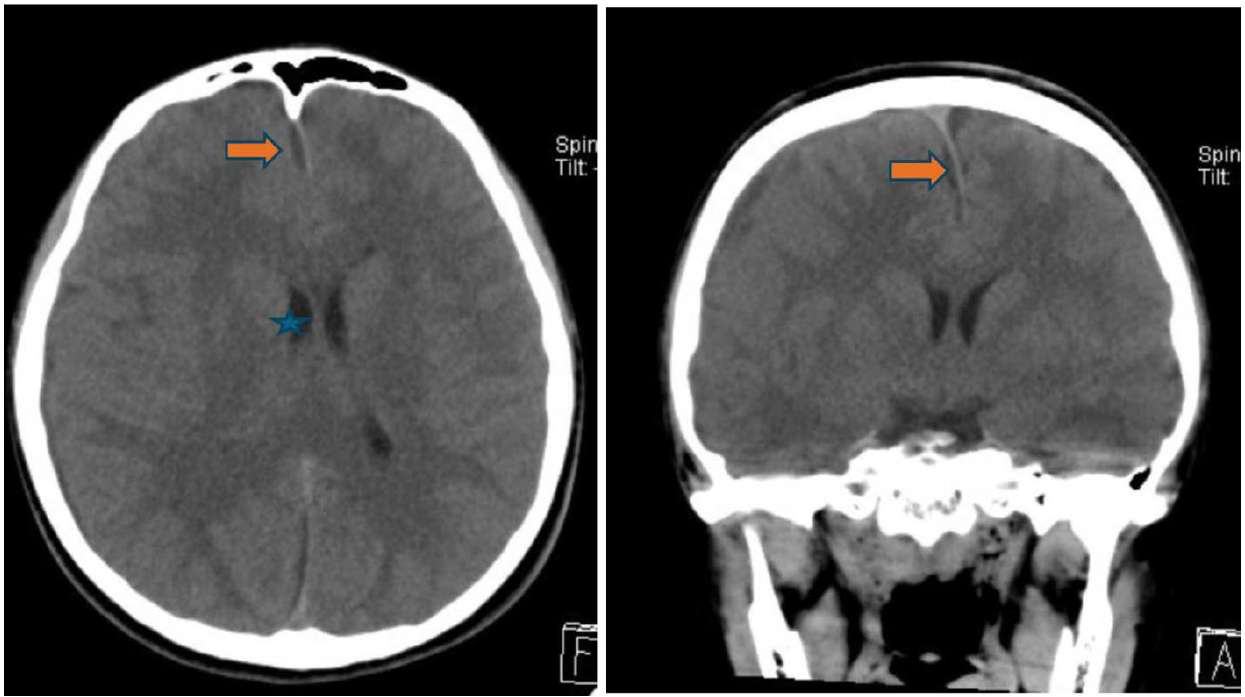

此病童的電腦影像,電腦斷層影像(非注射對比顯影劑),在冠狀切面(圖一)清楚呈現顏面部上頜竇(maxillary sinus)、鼻腔、篩竇(ethmoid sinus)、蝶竇(sphenoid sinus)等腫脹與不均值等病灶,且與健側對照,佐以軸狀切面影像,額竇(frontal sinus)的腫脹與不均值密度病灶(圖二)能較清楚呈現。進一步思考,病童呈現“雙眼球無法往左側移動”“頭痛且意識狀況異常”等,循著解剖器官組織的概念,審視眼部的影像,右眼框骨頭附近篩竇組織腫脹(圖一),審視腦部的影像,不管是軸狀面或是冠狀面影像(圖三),腦部組織腫脹且“推擠”至左側腦部呈現中線偏移。在部分腦部頂葉(parietal lobe)的影像(圖四),呈現相較低密度的“液體”狀成像,結合病童病史和抽血報告,積液部分疑似蓄膿,鑑別診斷可與慢性出血的稍高或等值密度做解析。另外,亦可藉由電腦軟體上可顯示的”Hounsfield unit, HU” 進行分析解讀。

圖一 、頭部電腦斷層冠狀切面(coronal view):右側上頷竇(maxilary sinus)內呈現有低密度且非均值的充填物(橘紅色箭頭)(正常影像,如左側上頷竇內空氣填滿(呈現黑色),診斷為右側上頷竇發炎。右側篩竇(ethmoid sinus)呈現腫脹(藍色星星)。右側眼眶骨內眼球和眼內肌無異常。

圖二、頭部電腦斷層軸狀切面(axial view):左圖,雙側蝶竇(sphenoid sinus) ,呈現不同密度的充填影像(橘紅色箭頭)。右圖,右側額竇(frontal sinus),呈現不同密度的充填影像(橘紅色箭頭)。